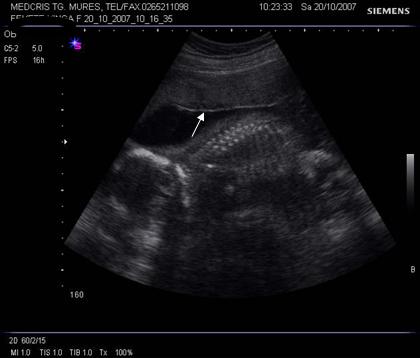

Fig. nr.211. Placenta grad. III la 41 saptamani gestationale, se remarca in structura placentara hiperecogenitati concentrice, in jurul unor zone relativ anecogene

Aparitia grd III inainte de 35 sapt, la maturatia placentei, a fost asociata cu greutate mica la nastere sau cu retard de crestere intrauterina.[9]

Calcificarile placentare (hiperecogene) sunt corelate cu hipertensiunea, retardul de crestere intrauterina si fumatul.